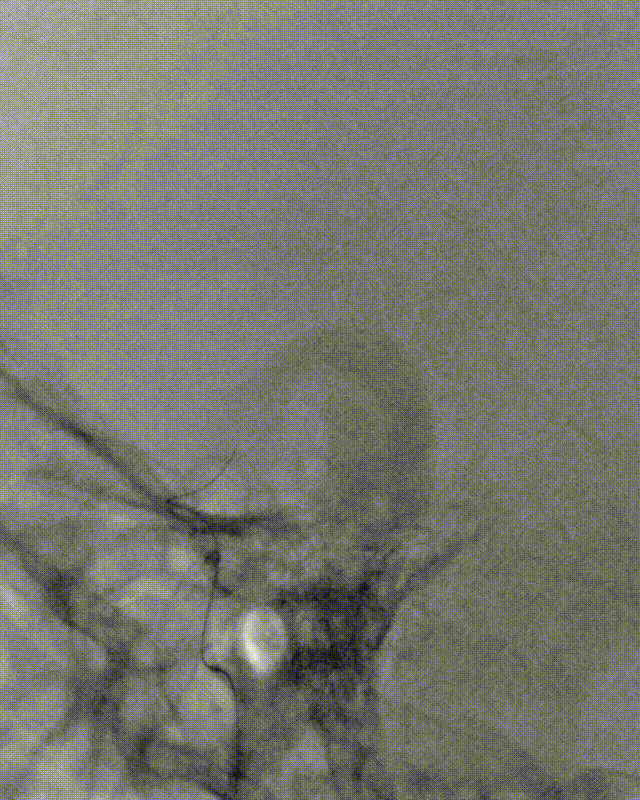

释放4×30mm取栓支架,可见支架局部打开不良,提示管腔重度狭窄。造影未见明显血栓征象,未行抽吸,拟直接行球囊扩张。

半回收取栓支架后,2.5×10mm低压球囊扩张狭窄处。

15min后,观察正侧位、3D旋转,可见狭窄较前明显改善。